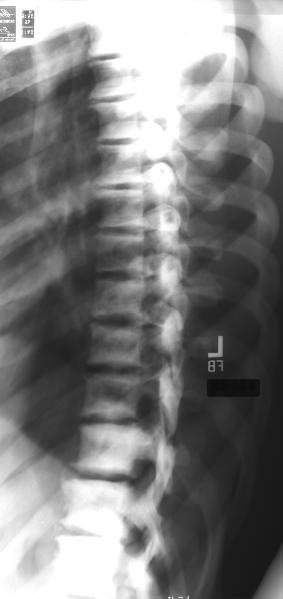

osteopetrosis2.jpg (14997 bytes)osteopetrosis4.jpg (20981 bytes)

After reviewing the above x-rays of this 40 year old male, the best diagnosis is:

Multiple myeloma

Prostate carcinoma

Osteopetrosis

Hyperparathyroidism